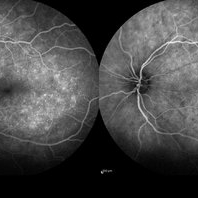

RPE rip in a case of Idiopathic polypoidal choroidopathy RPE rip in a case of Idiopathic polypoidal choroidopathyOct 23 2022 by Anjana Mirajkar, MS Ophthalmology Montage of Fluorescein angiography in a of 61 year old male with RPE rip in a case of Idiopathic Polypoidal Choroidopathy. Photographer: Dr. Anjana Mirajkar -Retina Foundation, Ahmedabad Condition/keywords: Idiopathic polypoidal choroidopathy, RPE rip